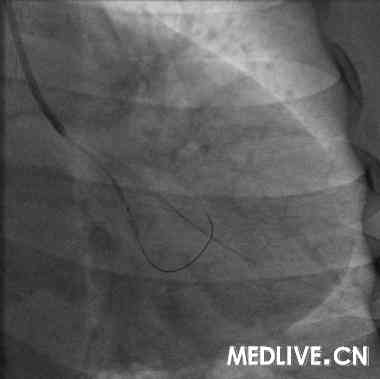

经右股动脉途径,6F,JR4.0引导管,HT BMW Universal引导丝顺利通过右冠闭塞病变部位,Diver血栓抽吸导管于病变部位及其近、远段部位连续抽吸,反复5次,造影可见右冠血流恢复,余狭窄最重部位直接植入Excel支架3.5*14mm,12atm释放,16atm原位后扩张,最重效果满意,右冠TIMI血流3级(图5-7)。

患者介入治疗过程中血压偏低,最低78/50mmHg,予静脉多巴胺持续泵入,依血压调整剂量;因冠脉内血栓负荷重,分别于冠脉内给予替洛非班(欣维宁),及静脉持续泵入;未预防缓慢心律失常,给予临时起搏器保驾。整个介入治疗过程顺利,未发生严重心律失常或无再流,予以适当补液,患者血压始终偏低,多巴胺最大20µg/kg/min。考虑患者冠脉双支病变,虽然右冠急诊介入治疗成功,仍给予了IABP辅助治疗。